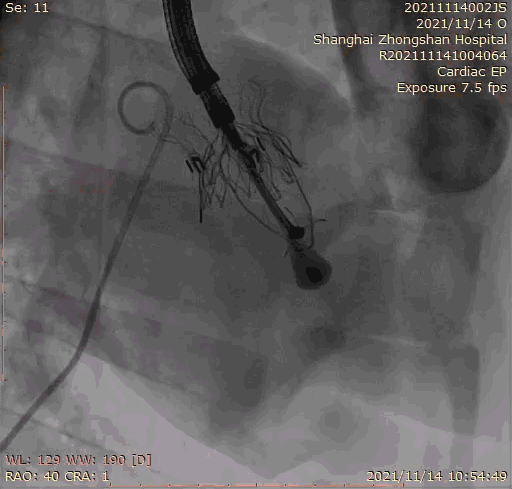

2021年11月14日星期日,復(fù)旦大學(xué)附屬中山醫(yī)院(以下簡稱中山醫(yī)院)葛均波院士團(tuán)隊(duì)成功應(yīng)用經(jīng)血管介入三尖瓣置換產(chǎn)品Lux-Valve Plus完成臨床前研究,并獲得圓滿成功!此次研究的成功預(yù)示經(jīng)血管三尖瓣產(chǎn)品Lux-Valve Plus已完成臨床前準(zhǔn)備,即將開啟后期的正式臨床研究!

上海中山醫(yī)院葛均波院士、錢菊英院長、周達(dá)新教授、潘文志教授、潘翠珍教授、李偉教授共同完成此次臨床前研究。術(shù)后葛均波院士對Lux-Valve Plus的器械操作性能給予了高度評價(jià),DSA和超聲影像也顯示出在本次研究中Lux-Valve Plus的安全性和有效性俱佳。

本次臨床前研究經(jīng)右側(cè)頸靜脈置入LuX-Valve Plus輸送系統(tǒng)可調(diào)彎鞘管,在DSA及超聲引導(dǎo)下將人工三尖瓣瓣膜植入到原有三尖瓣位置,利用獨(dú)特的錨定技術(shù)將人工瓣膜支架可靠固定在預(yù)定的位置。